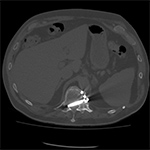

|

| 70 year-old man with history of L1 and L3 injury and T11-L3 spinal fusion in the 1990's. Recent worsening of chronic lower back pain. Standard radiographs (left two images) show a vertebral body corpectomy cage at T12-L3 with placement of a left lateral side plate at the same levels. There are two proximal screws at T12, one of which enters the spinal canal as shown on subsequent CT (right two images). There are two distal screws at L3, the most distal of which enters the L3-4 disk space (lateral radiograph). |